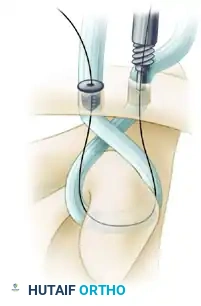

6. Graft Preparation and Passage

A robust graft, such as a semitendinosus allograft, is prepared with whipstitches at both ends using high-strength nonabsorbable suture.

* Pass a shuttling suture (e.g., a looped passing wire or heavy suture) beneath the coracoid using the previously created path.

* Shuttle the tendon graft beneath the base of the coracoid. Ensure the graft lies flat against the undersurface of the coracoid to maximize the contact area and prevent abrasion.

Graft passage beneath the base of the coracoid. The graft must be seated flush against the bone to ensure biomechanical stability and prevent neurovascular impingement.

- Routing the Limbs:

- Pass the lateral limb of the graft (along with its sutures) superiorly through the first (posterior/conoid) tunnel. Cross it posteriorly so that it will ultimately form a figure-of-eight configuration.

- Feed the medial limb of the graft through the anterior (trapezoid) tunnel. Do not cross this suture; pass it directly so that it forms a circular configuration.

Graft crossing technique: The lateral limb is crossed posteriorly to create a figure-of-eight, mimicking the complex multi-planar vectors of the native CC ligaments.